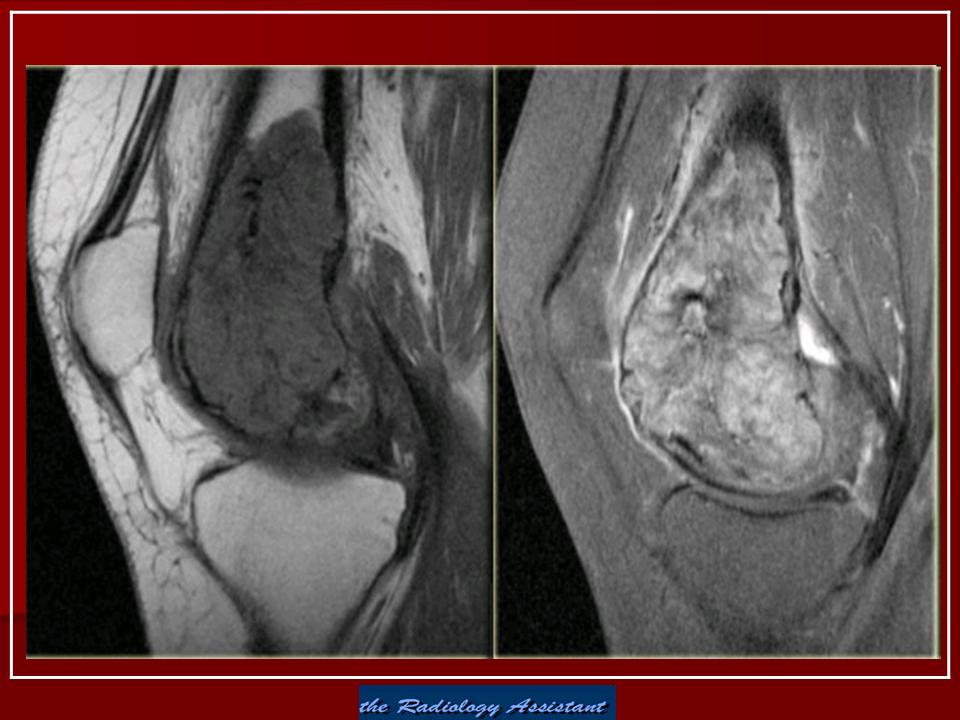

Гигантоклеточная опухоль.